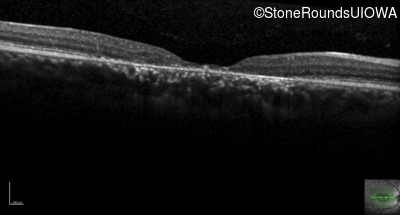

AR Stargardt Disease (IIA)

Age at visit: 29 years (Visit 2)

Age at visit: 30 years